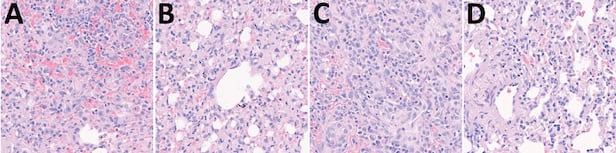

A는 코로나 델타 변이에 직접 감염된 실험용 개의 폐조직이며 B는 델타 변이에 전파 감염된 개의 폐조직이다. C와 D는 각각 오미크론 변이에 감염된 실험용 개와 전파 감염된 개의 폐조직이다. 모든 사진에서 대식세포와 림프구 등이 증식하는 바이러스성 폐렴 증상이 관찰된다./서울대·전북대 연구진 제공

모든 개에게서 체중 감소나 발열 등 코로나 감염의 임상 증상이 보이지는 않았지만 폐에서 감염 합병증인 바이러스성 폐렴 증상이 확인됐다. 개의 콧물을 통해 코로나 바이러스가 배출됐으며, 개들끼리 직접 접촉하면서 건강했던 정상견도 바이러스에 감염된 것으로 나타났다.